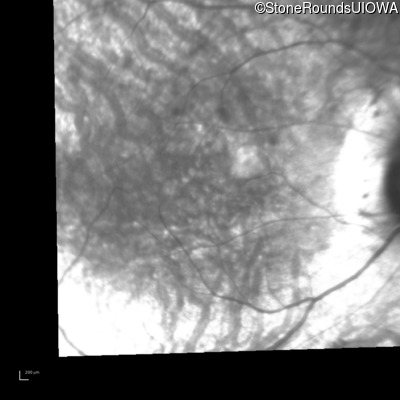

Infrared Fundus Photograph - Left - 20/50

Exemplar